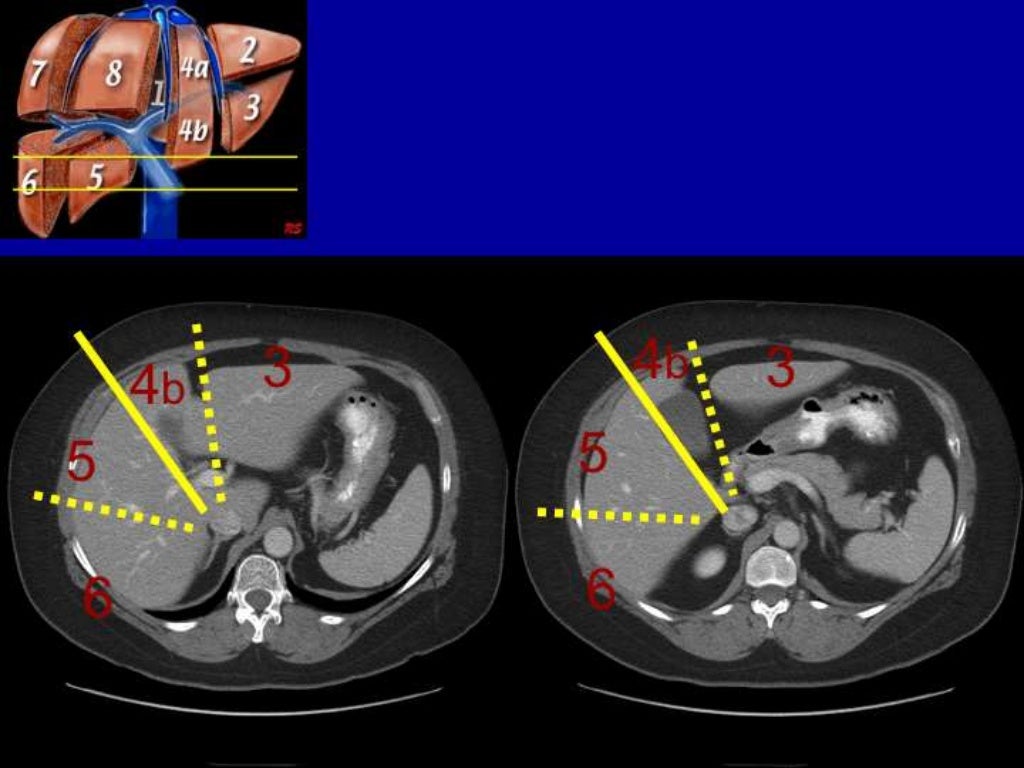

Ct Anatomy Of Hepatobiliary . See annotated images of normal and abnormal anatomy, pathology, and pacs viewer. learn how to evaluate the liver, gallbladder, bile ducts, and pancreas on ct scans. ct and mr cholangiography are minimally invasive methods that provide precise depiction of the biliary system. the use of mr imaging and ct in the evaluation of biliary disease is discussed and illustrated in terms of optimal technique, benefits, and. learn about the anatomy, physiology, and pathology of the hepatobiliary system, including the liver,. learn how to divide the liver into eight functionally independent segments according to couinaud classification. learn about the normal and variant anatomy of the biliary tree, including the common bile duct (cbd) diameter and the common confluence of the hepatic.

learn how to divide the liver into eight functionally independent segments according to couinaud classification. learn how to evaluate the liver, gallbladder, bile ducts, and pancreas on ct scans. learn about the anatomy, physiology, and pathology of the hepatobiliary system, including the liver,. learn about the normal and variant anatomy of the biliary tree, including the common bile duct (cbd) diameter and the common confluence of the hepatic. the use of mr imaging and ct in the evaluation of biliary disease is discussed and illustrated in terms of optimal technique, benefits, and. ct and mr cholangiography are minimally invasive methods that provide precise depiction of the biliary system. See annotated images of normal and abnormal anatomy, pathology, and pacs viewer.